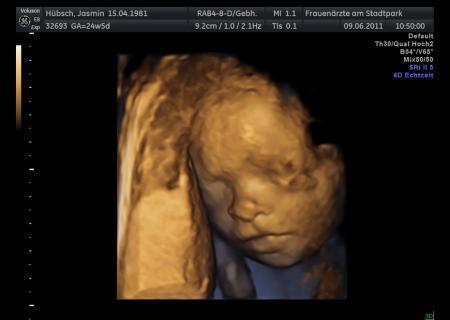

Hallo, hatte heute meine VU mit wunderschönen Bilder meines Sohnemannes, die ich einfach mal zeigen muß...... hat noch jemand von euch Nachts mit Schmerzen in den Beinen zu Kämpfen? Keine Krämpfe sondern richtige schmerzen und Empfindungsstörungen... Lg Jasmin

Bild zu Meld mich auch mal wieder!!!! - Forum für September - Mamis

Ich finde das sehr interessant mit den 3D-Aufnahmen. Musst du dafür zu einem Spezialisten? Kostet das extra?

Ein süßes Foto! Glückwunsch Aber kurz noch als Tipp: Mach deine Daten unkenntlich auf den Bildern die du hochlädst. Die Bilder hier sind für die ganze Welt zugänglich. Hast du wegen den Schmerzen in den Beinen mal mit deinem FA gesprochen? Klingt ja garnicht gut. Vielleicht Magnesiummangel